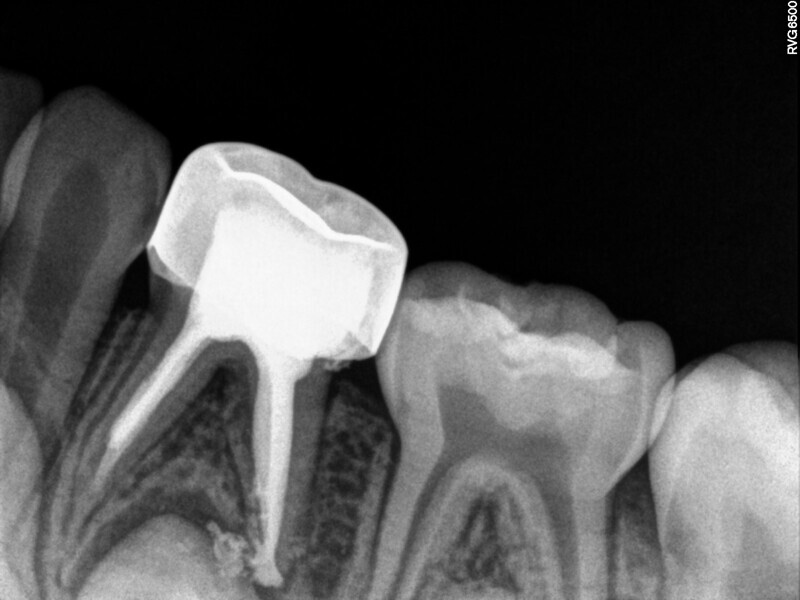

Ce patient âgé de 4 ans et 6 mois présentait une douleur constante qui était apparue spontanément au niveau de la première molaire temporaire inférieure gauche, et persistait depuis plusieurs jours. Toutefois, aucun œdème facial ou gonflement du versant vestibulaire de la gencive n’était visible. Des caries profondes étaient présentes, mais il n’y avait ni mobilité dentaire ni profondeur de poche importante au sondage. La radiographie montrait un risque d’effraction de la cavité pulpaire lié à la lésion carieuse, et une atteinte de la zone de furcation correspondant à un défaut osseux. Une pulpectomie était le traitement de choix. L’élimination de la lésion carieuse a entraîné une exposition de la pulpe, mais aucun saignement n’a été observé. Une nécrose pulpaire a été diagnostiquée. Quatre canaux, deux mésiaux et deux distaux, ont été localisés et la dent a été obturée. Lors du second rendez-vous, la dent était asymptomatique et elle a été restaurée au moyen d’une couronne en acier inoxydable. À la visite de suivi à 30 mois, la dent ne présentait aucun symptôme et la radiographie a montré un processus éruptif normal.

Cas 4 (Figs. 14 à 18)